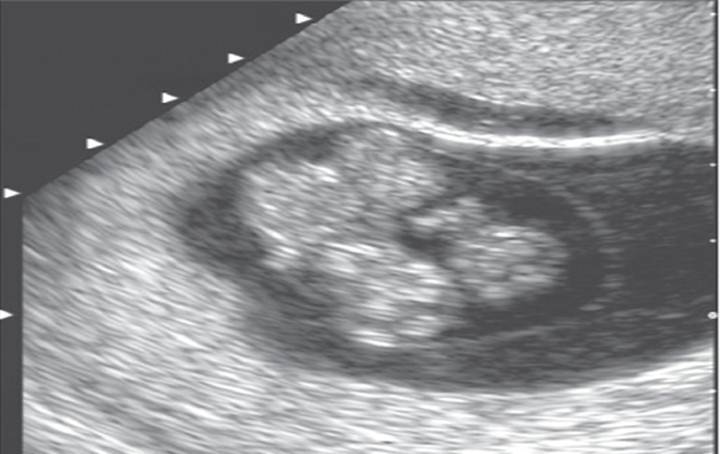

Choroid plexus cysts